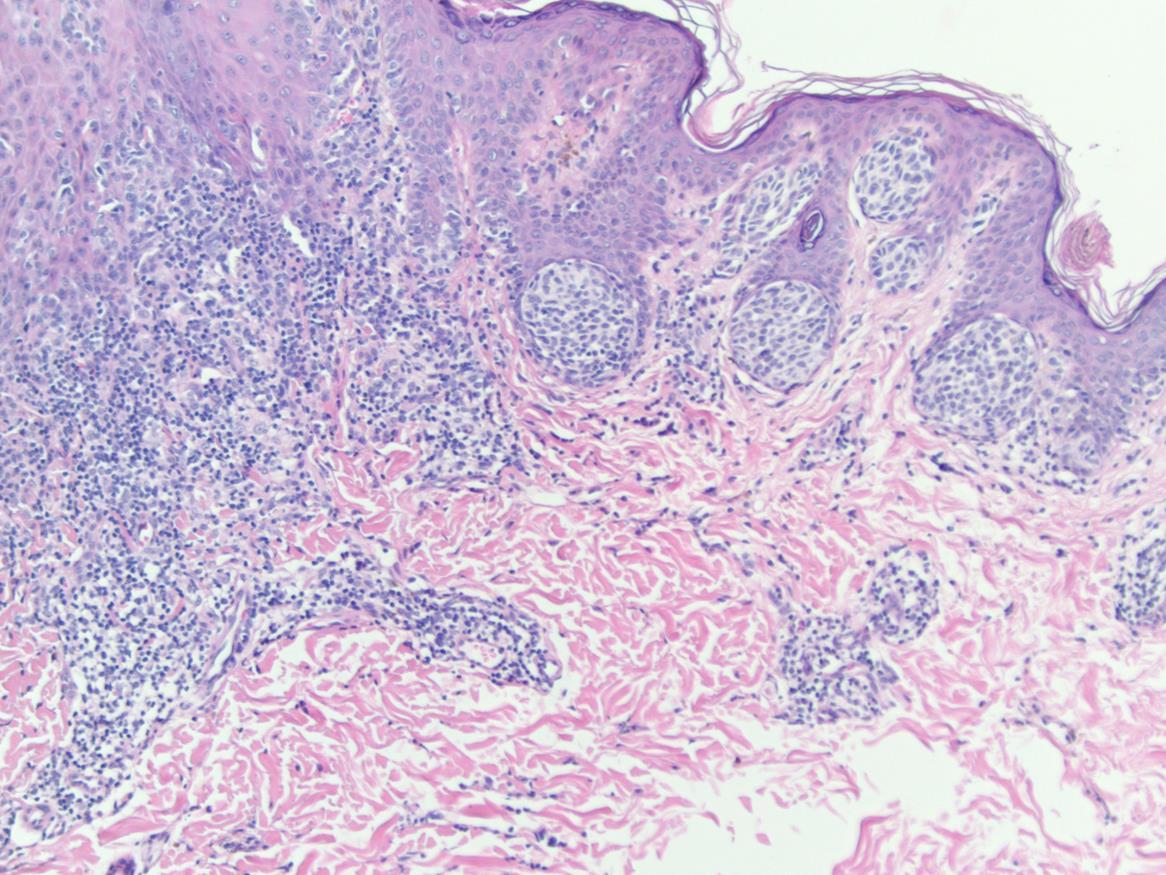

• Trichoblastoma and trichoepithlioma

• Dual differentiation towards follicular germinative epithelium and follicular papillae

• Head and neck

• Can be associated with naevus sebaceous and syndromes (BSS)

• Well defined, nodular nested proliferation of basaloid cells with follicular differentiation

• Palisading of cells

• Papillary mesenchymal bodies

• No cytonuclear atypia

• No retraction – dd with BCC

• Contain Merkel cells – CK20